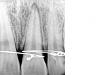

Romario Опубликовано 23 апреля, 2011 Поделиться Опубликовано 23 апреля, 2011 Парень..20 лет...тупой удар в губу....со слов появилась небольшая подвижность зуба 2.1...зашинировали в члх вчера...2 степень подвижности...перкуссия слабоболезнена...маргинальная десна слегка гиперемирована..самостоятельных болей не отмечал...на темп.раздражители реакции нет...в цвете не изменен...эод и пробы не проводил...раньше назначили нпвс и хлорегексидин.....отпустил с условием если боли появятся-явиться.... Через какое время рекомендуете провести осмотр?Кто видит трещину?трещины не вижу, периодонтальная щель конечно увеличена особенно с дистальной стороны Ссылка на комментарий

juli63 Опубликовано 23 апреля, 2011 Поделиться Опубликовано 23 апреля, 2011 трещину не вижу. на темепр. раздражители не реагирует, т.к. скорее всего там контузия нервной ткани(а ее чувствительность может возвращаться 9-12 мес).судя по снимку тут скорее люксация(имхо). какой звук при перкуссии? шинирование лигатурное? поправьте если что?. оно еще больше травмирует. нужно нерегидное. на 7-10 дней. соответственно наблюдать через-1-2 нед. если раньше не прибежит. а дальше будем см по ситуации. если будет 2 признака в сторону некроза-нужно эндо(типа изменился цвет+положит перкус.)... Ссылка на комментарий

akakii Опубликовано 23 апреля, 2011 Поделиться Опубликовано 23 апреля, 2011 повторный осмотр через 3-4 недели. если динамика положительная, тогда следующий визит через полгода. заново проводим все диагностические мероприятия и смотрим их динамику. результаты диктуют дальнейшую тактику. Согласен, что лигатурное шинирование само по себе может оказывать отрицательное влияние на периодонт зубов.трещину не вижу. Ссылка на комментарий